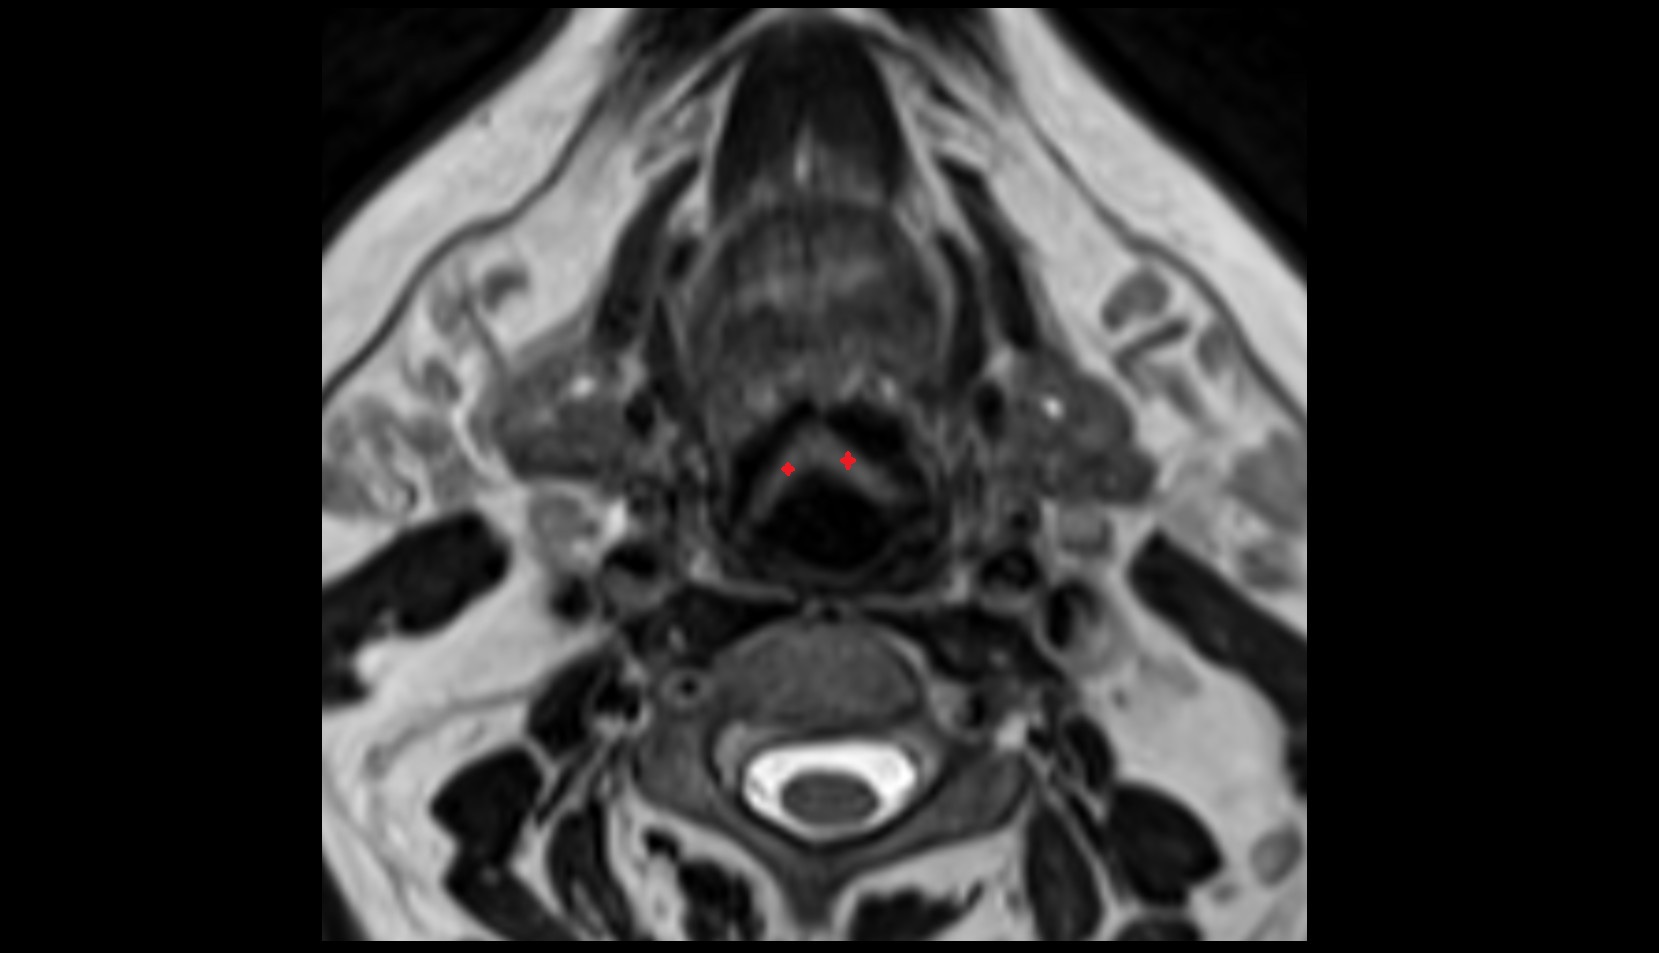

- Peripheral zone of prostate

- Anterior Fibromuscular Stroma of prostate

- Central zone of prostate

- Transitional zone of prostate